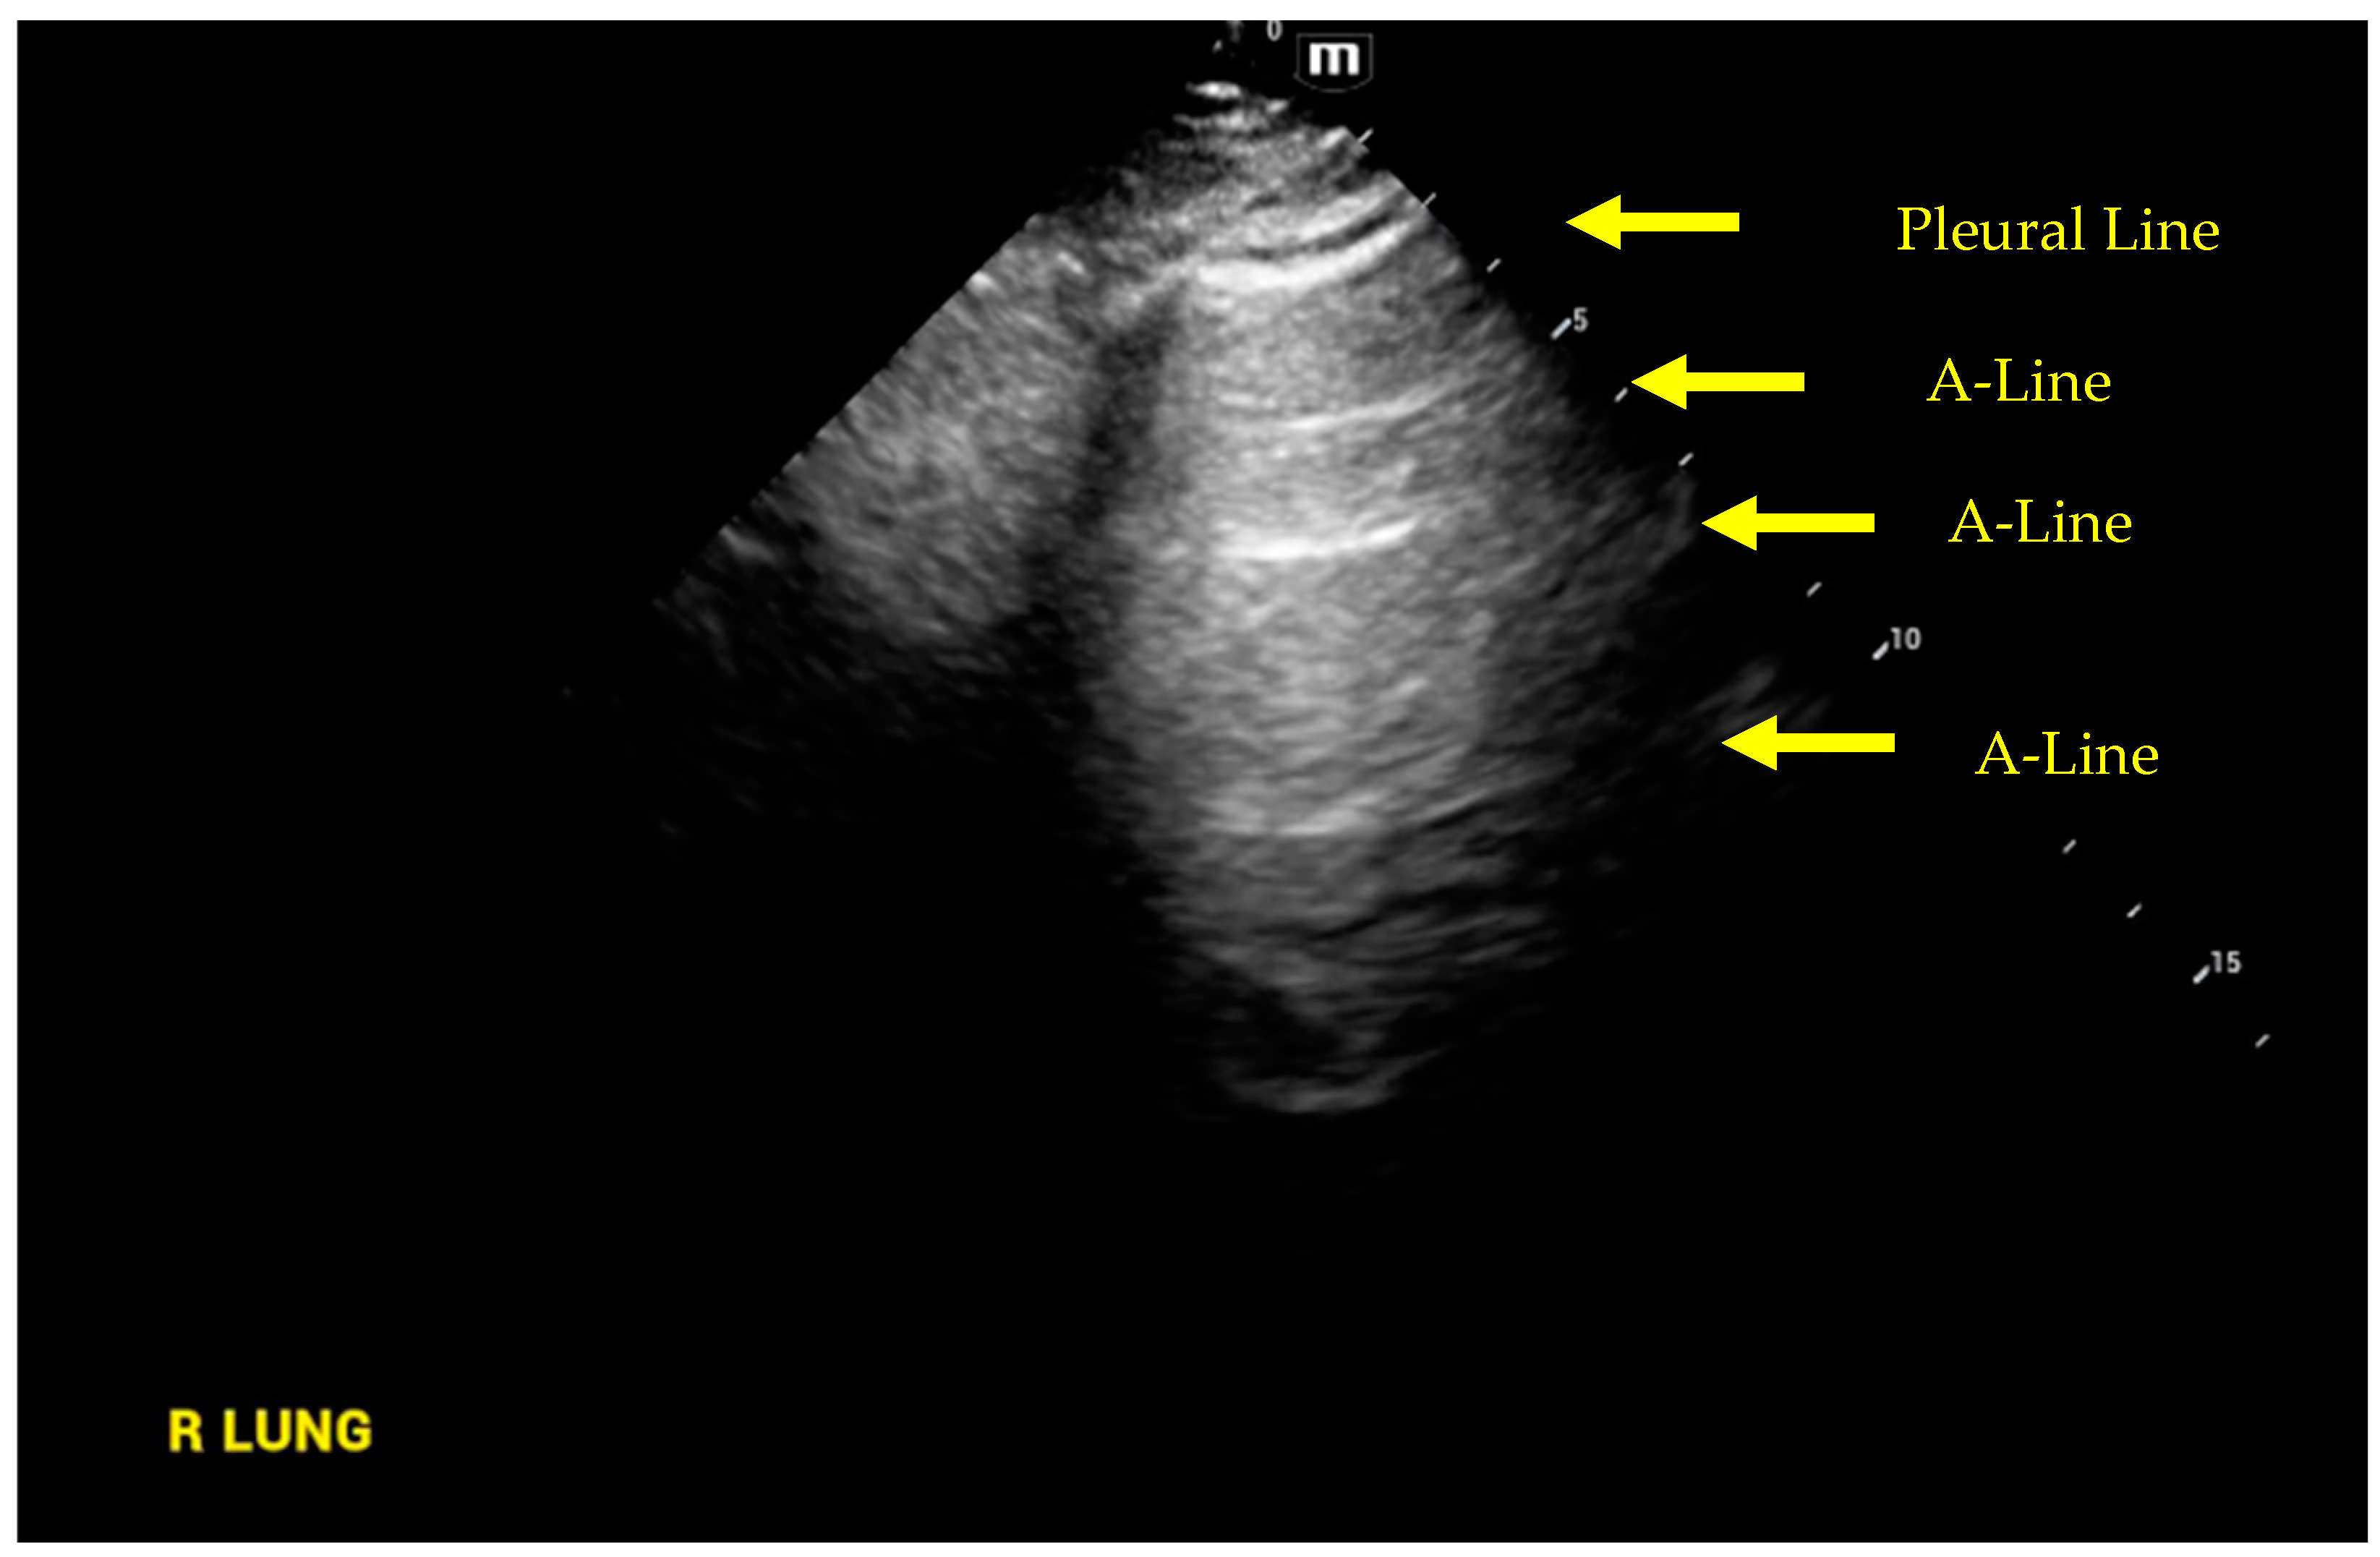

4. Lung Ultrasound

- Volpicelli, G.; Elbarbary, M.; Blaivas, M.; Lichtenstein, D.A.; Mathis, G.; Kirkpatrick, A.W.; Melniker, L.; Gargani, L.; Noble, V.E.; Via, G.; et al. International evidence-based recommendations for point-of-care lung ultrasound. Intensive Care Med. 2012, 38, 577–591. [Google Scholar] [CrossRef]

- Lichtenstein, D.A.; Meziere, G.A. Relevance of lung ultrasound in the diagnosis of acute respiratory failure: The BLUE protocol. Chest 2008, 134, 117–125. [Google Scholar] [CrossRef] [PubMed]

- Lichtenstein, D.A.; Meziere, G.A.; Lagoueyte, J.F.; Biderman, P.; Goldstein, I.; Gepner, A. A-lines and B-lines: Lung ultrasound as a bedside tool for predicting pulmonary artery occlusion pressure in the critically ill. Chest 2009, 136, 1014–1020. [Google Scholar] [CrossRef] [PubMed]